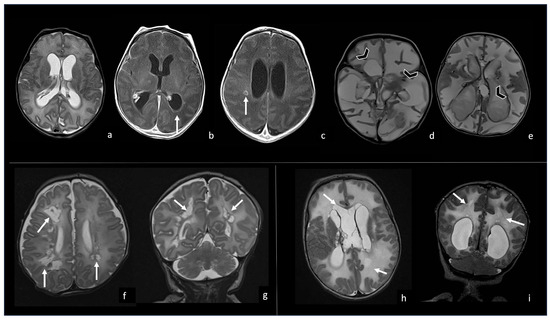

6.2. Infarcts

7. Peculiar MRI Patterns

7.1. Group B Streptococcus

7.2. Listeria Monocytogenes

7.3. Gram-Negative Bacteria and Abscesses